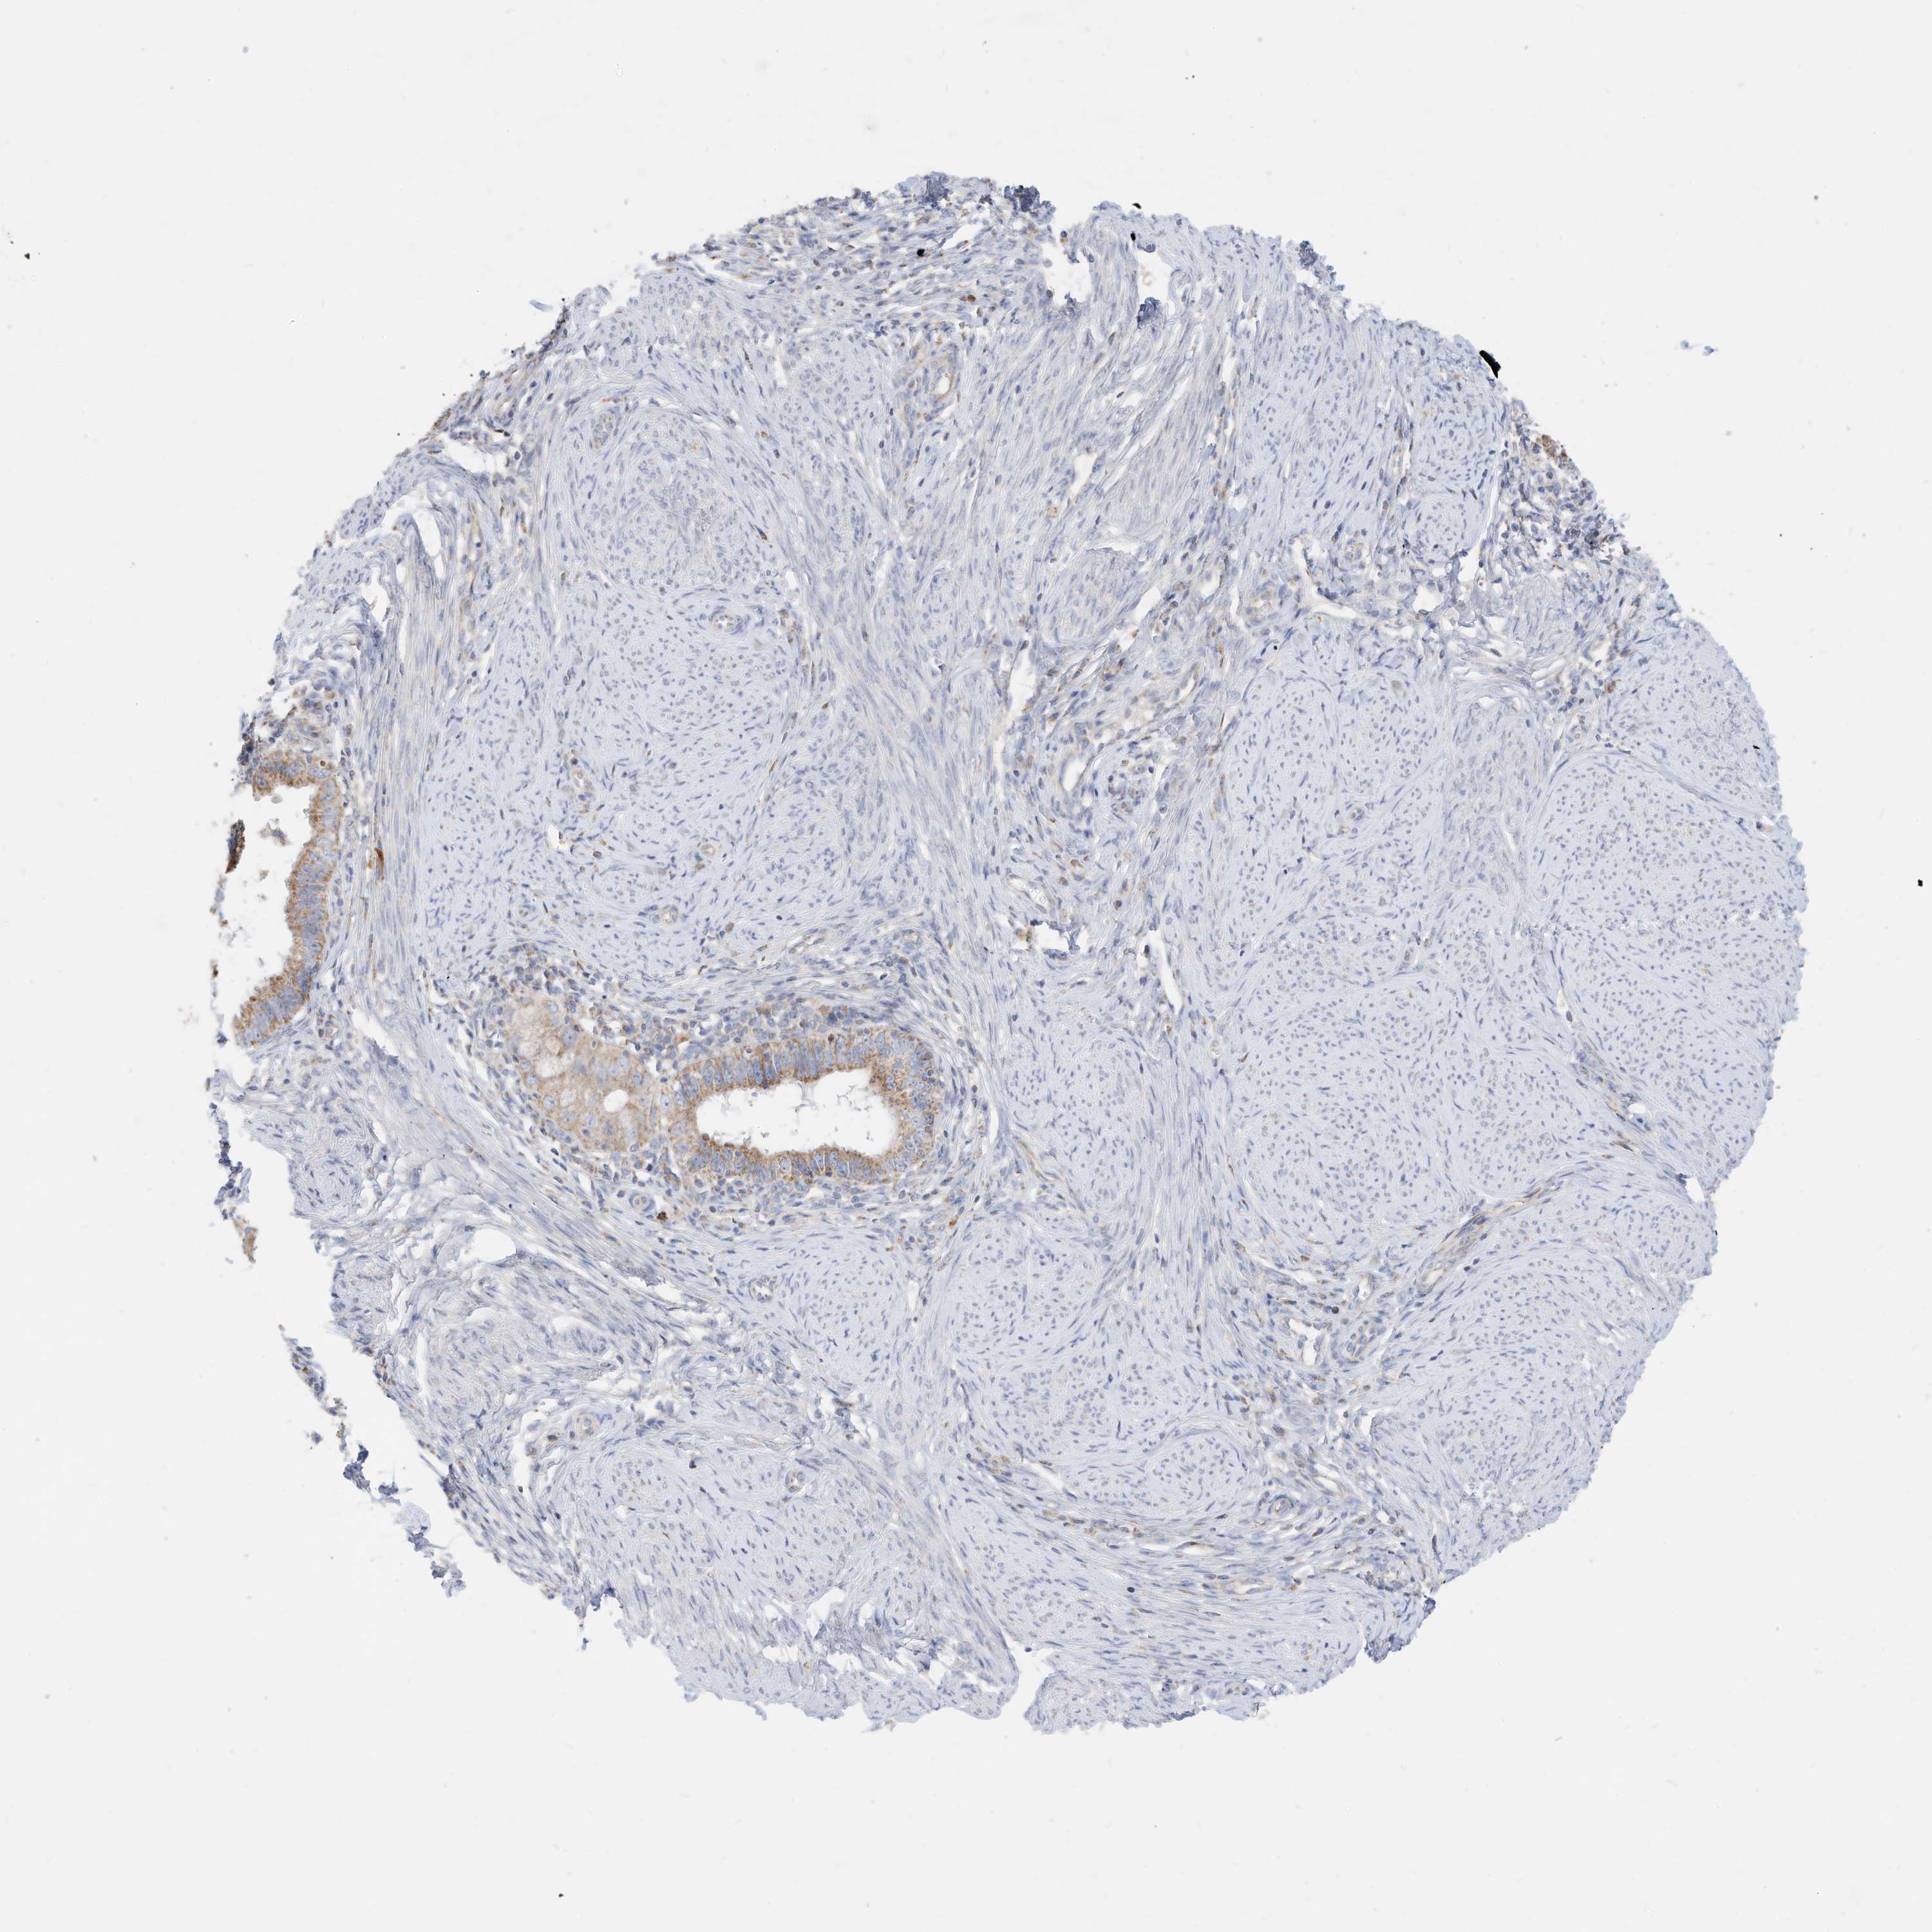

CERVICAL CANCER - Protein expressioni

A mouse-over function shows sample information and annotation data. Click on an image to view it in a full screen mode. Samples can be filtered based on level of antibody staining by selecting one or several of the following categories: high, medium, low and not detected. The assay and annotation is described here.

Note that samples used for immunohistochemistry by the Human Protein Atlas do not correspond to samples in the TCGA dataset.

Antibody stainingi

Antibody staining in the annotated cell types in the current human tissue is reported as not detected, low, medium, or high, based on conventional immunohistochemistry profiling in selected tissues. This score is based on the combination of the staining intensity and fraction of stained cells.

Each image is clickable and will lead to virtual microscopy that enables deeper exploration of all samples and also displays staining intensity scores, fraction scores and subcellular localization as well as patient and tissue information for each sample.

Antibody HPA030345

Squamous cell carcinoma, NOS

Adenocarcinoma, NOS